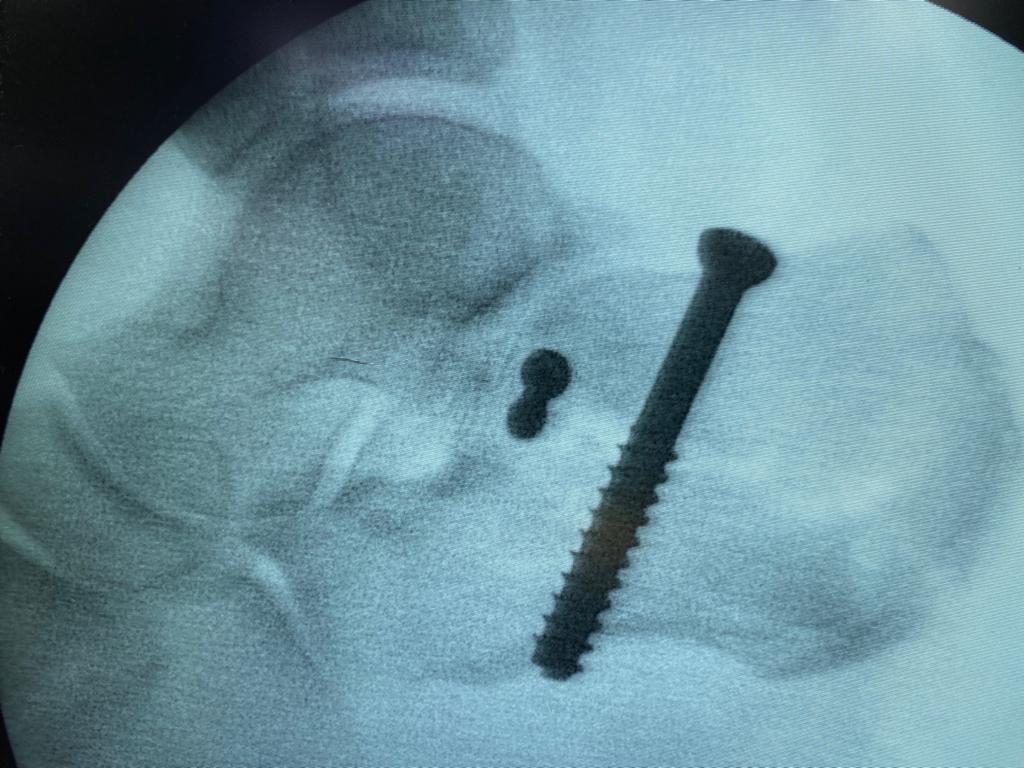

Não bastasse o problema de seu desmaio, Cleiton, nesse período de afastamento do trabalho ainda sofreu um acidente doméstico e fraturo um de seus pés há cerca de dois meses atrás, tendo ele fraturado e passado por um procedimento cirúrgico na Santa Casa de Misericórdia de Catalão.